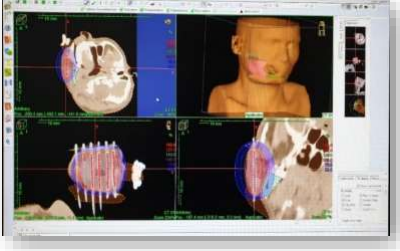

In the 1990s, technological and computer treatment planning advances led to the development of Intensity-modulated radiotherapy {IMRT}. The technique of IMRT is more complex and resource-intensive than 3DCRT. It uses a CT-based inverse planning process to deliver ionizing radiation conformally to the target by altering the beam intensity using tungsten-based multi-leaf collimators. Standard IMRT techniques are referred to as sliding window, step, and shoot.

IMRT is a specialized form of 3D-CRT that allows radiation to be more exactly shaped to fit the tumor. The radiation beam in IMRT can be split into many tiny beamlets and the intensity of each beamlet can be modulated. Using IMRT it is possible to further limit the amount of radiation received by normal tissue located in the close proximity of the tumor. The ability to optimize the intensities of each beamlet leads to attaining desired tumor control and minimal toxicity to normal tissues. With respect to oral cavity cancer, IMRT offers the opportunity to diminish normal tissue toxicities, including damage to major salivary glands (xerostomia), to the mandible (osteoradionecrosis) and to the spinal cord(myelopathy).[23,24]

IMRT requires an exact determination of the tumor location and a thorough knowledge of the processes of likely infiltration and spread.[25] International Commission on Radiation Units and Measurements created terminology for use across institutions. Definitions include gross tumor volume (GTV), clinical target volume (CTV), and planning target volume (PTV).26 The GTV pertains to gross disease identified by clinical workup (physical examination and imaging), CTV includes the GTV and any areas at risk for microscopic disease, and PTV is an expansion of the CTV by a margin to account for patient or organ motion and day to day set up variation. ICRU 83 (Annexure VI) presents updated definitions for IMRT and assorted volumes that will form the skeleton of the treatment plan.[27]